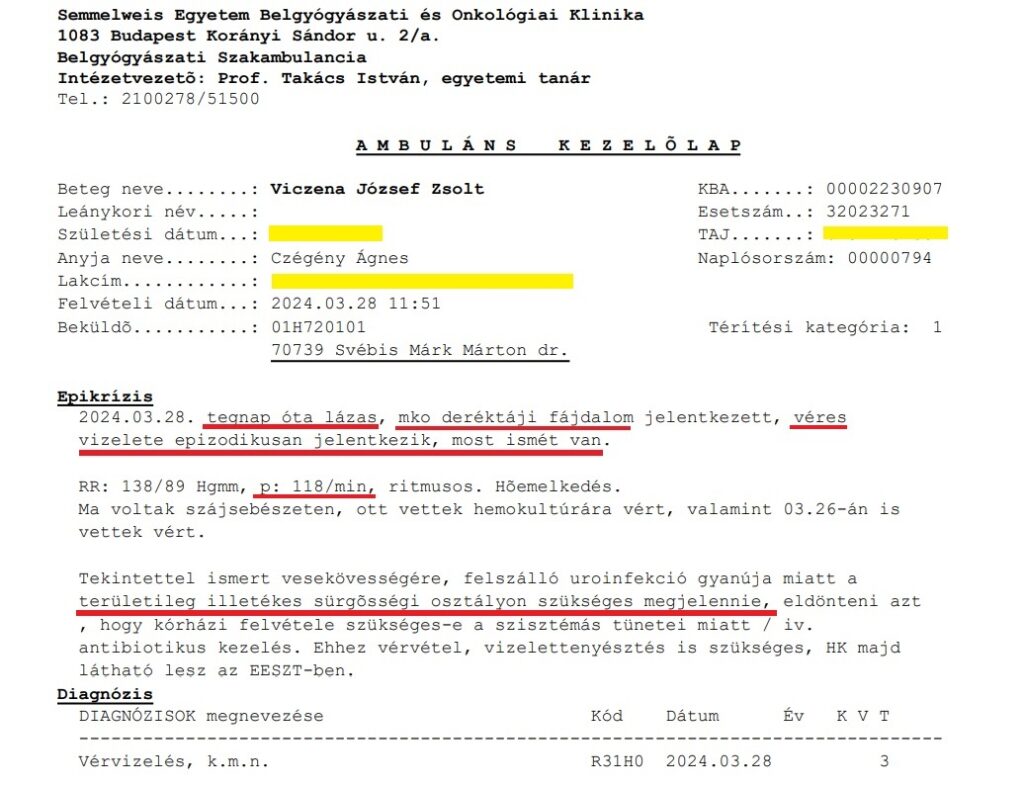

Ezután az I. számú Belgyógyászati klinikára a fiam mindenképp át akart menni, hiszen ott volt gyakorlatilag vérmérgezéses állapotban egy folyosón és senkit nem érdekelt a továbbiakban. Akkor tudtuk meg, hogy Dr. Ledó Nóra szabadságon van. A recepciós hölgy, amikor meglátta a fiamat, azonnal rohant, „úristen” felkiáltással, hogy hogy néz ki a fiam, egymás után hívta fel az orvosokat. Nagyobb felelősségérzete volt, mint az összes orvosnak együttvéve. Végül egyik kollégája Dr Svébis Márk fogadta a fiamat. Azonnal láttuk, hogy nem érti, mi történt itt, hogy történhetett meg, hogy hosszú hetek óta ide jár, ilyen szörnyű leletei és állapota van és nem kezelte a kolléganője, sőt még aznap is távolból elutasította a kórházi felvételt…Mégis Svébis Márk is képes volt elküldeni területileg illetékes sürgősségire hivatkozva a 4 napos húsvéti ünnep előtt a szeptikus állapotban levő fiamat!!! „Felszálló uroinfekció!”- ami már valójában februárban „felszállt a vesékbe… Miért nem tette meg ő? A szakklinika orvosa? Munkaidő volt! Azonnali labor, vizeletvizsgálat helyett elküldte, így nem készültek laboreredmények a szeptikus állapotú fiamnál! (Ez nem véletlen ám.) Mit műveltek velünk, csak azért, hogy ne derüljön ki, Ledó Nóra hetek óta nem kezel egy akut állapotú beteget?

Alább a 2024.05.21-én készült CTA egy képe a vesékről, vesemedencéről: